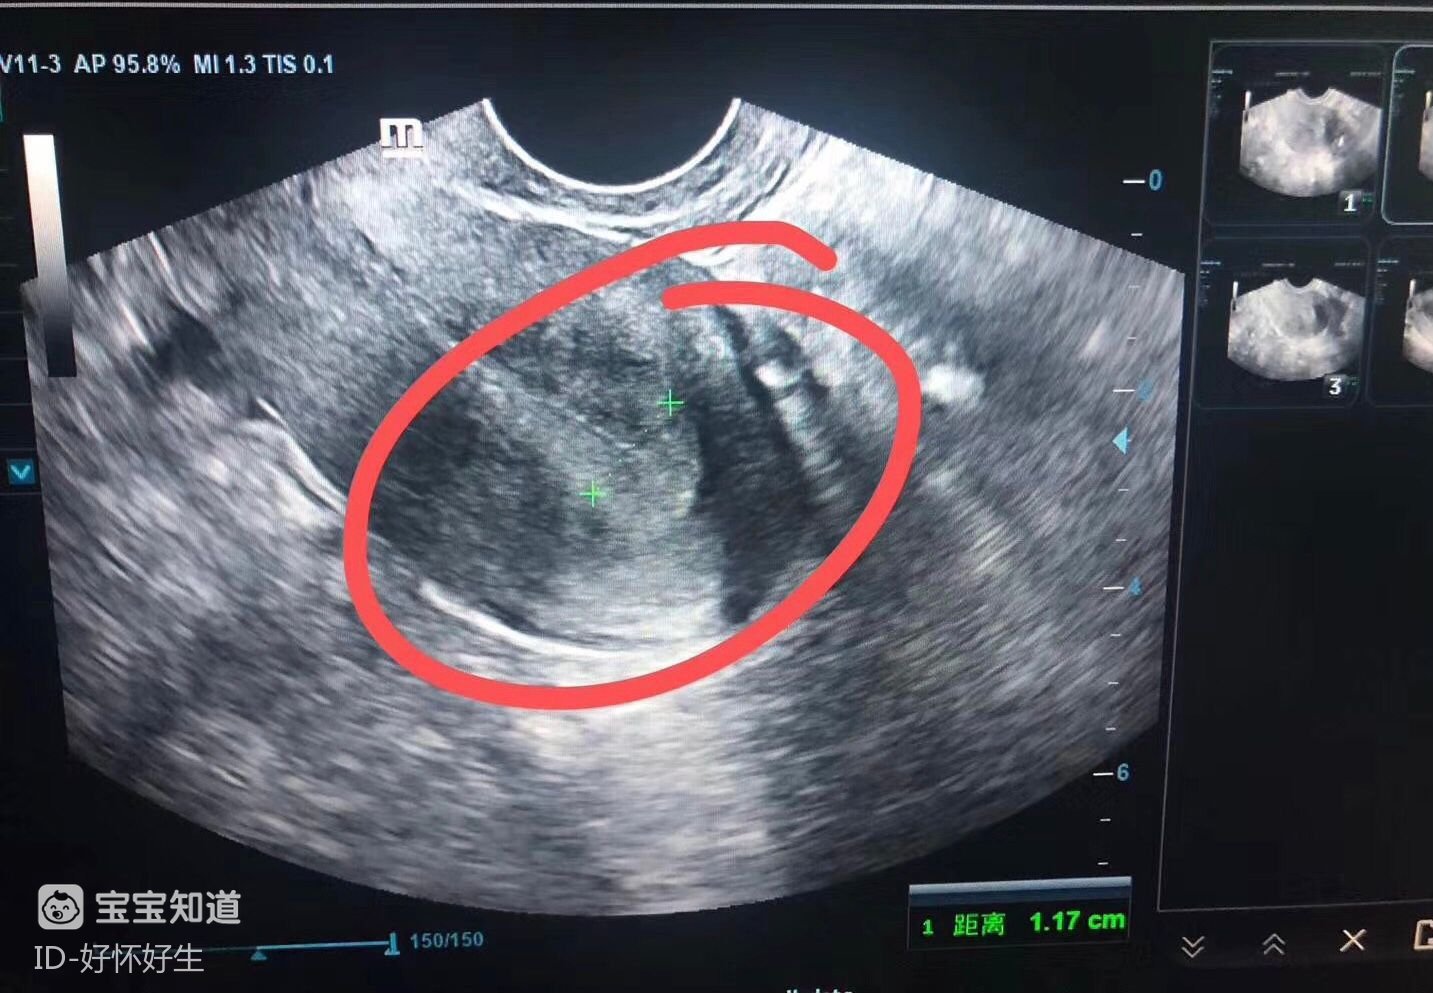

然后,促排期間要定期抽血查激素和照B超,監(jiān)測卵泡發(fā)育情況,當(dāng)卵泡成熟了就打夜針促進(jìn)排卵,打夜針后34-36小時取卵,取卵當(dāng)天,男方取精。